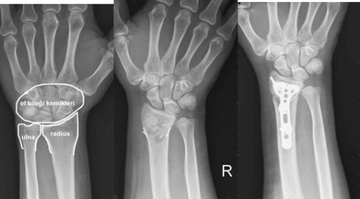

Doku zedelenmesi yaşayan birisi olarak, yumuşak doku zedelenmesi ilaçları hakkında bilgi almak istiyorum. Özellikle bu tür yaralanmalar için hangi ilaçların etkili olduğu ve ne zaman kullanılmaları gerektiği önemli. Ayrıca, bu ilaçların yan etkileri nelerdir?

Doku Zedelenmesi ve İlaçlar

Edim, yumuşak doku zedelenmeleri genellikle kas, tendon ve bağ dokularında meydana gelen yaralanmalardır. Bu tür yaralanmalar için çeşitli ilaçlar ve tedavi yöntemleri bulunmaktadır.

İlaç Türleri

1. Ağrı Kesiciler: Non-steroidal anti-inflamatuar ilaçlar (NSAID'ler) genellikle ağrı ve iltihaplanmayı azaltmak için kullanılır. Örneğin, ibuprofen veya naproksen bu gruptadır.

2. Kas Gevşeticiler: Kas spazmlarını azaltmak için kullanılabilir. Baclofen veya tizanidin gibi ilaçlar bu amaçla tercih edilebilir.

3. Topikal Kremler: Yaralanma bölgesine uygulanan ağrı kesici veya anti-inflamatuar kremler de mevcuttur. Diclofenac jel bu tür bir örnektir.

Kullanım Zamanı

İlaçların kullanımı, yaralanmanın ciddiyetine ve belirtilere göre değişir. Genel olarak, başlangıçta ağrı ve şişlik varsa NSAID'ler ile tedaviye başlanabilir. Kas spazmları varsa kas gevşeticiler devreye girebilir. Topikal kremler, belirtiler hafif olduğunda veya lokalize ağrı varsa etkili olabilir.

Yan Etkiler

İlaçların yan etkileri kişiden kişiye değişebilir. NSAID'lerin yan etkileri arasında mide rahatsızlıkları, böbrek sorunları ve kanama riskinin artması sayılabilir. Kas gevşeticilerin ise baş dönmesi, uyku hali ve bağımlılık potansiyeli gibi yan etkileri olabilir. Topikal kremlerin yan etkileri genellikle lokal alerjik reaksiyonlar şeklinde ortaya çıkabilir.

Herhangi bir ilaç kullanmadan önce mutlaka bir sağlık profesyoneline danışmanız önemlidir. Geçmişte yaşadığınız yaralanma ve genel sağlık durumunuz, hangi ilaçların uygun olacağını belirlemede önemli rol oynar. Geçmiş olsun!